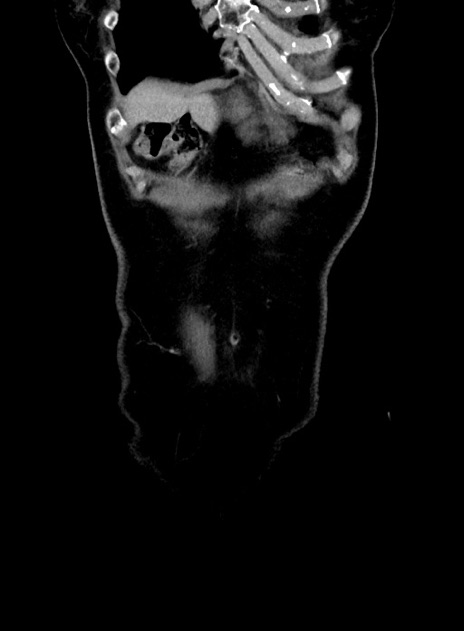

横断像

【症例】 60歳代女性

【主訴】むかつき、みぞおちの痛み

【現病歴】3日前よりむかつきがあり、食事がとれない。

【既往歴】糖尿病

【身体所見】発熱なし、心窩部圧痛軽度あるも、腹膜刺激症状なし。

【データ】WBC 7400、CRP 1.92